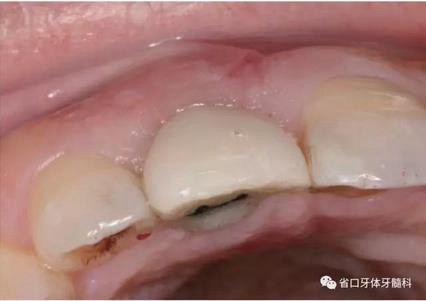

圖1 術(shù)前口內(nèi)照

圖2 術(shù)前口內(nèi)照

圖3 術(shù)前口內(nèi)照

1.?病例簡介 43歲女性患者,主拆:右上前牙松動(dòng)不適數(shù)日要求修復(fù)?,F(xiàn)病史:患者數(shù)年前右上前牙因“齲壞”于外院行根管治療(具體不詳),數(shù)日前牙冠松動(dòng)不適,現(xiàn)覺影響咀嚼及美觀,遂來我院要求進(jìn)一步診治。否認(rèn)高血壓、心臟病等重大疾病,否認(rèn)結(jié)核、肝炎等傳染病史,否認(rèn)手 術(shù)、輸血史等,未發(fā)現(xiàn)藥物過敏。無吸煙習(xí)慣。臨床檢查:口外觀顏面基 本對稱,皮膚無紅腫破潰,顳下頜關(guān)節(jié)區(qū)無彈響、雜音、壓痛,開口度約 37mm,開口型“↓”,頜下、刻下和頸部未及腫大淋巴結(jié)。中位笑線??趦?nèi)檢查,口腔衛(wèi)生可,色素(+),BOP(-),PD=2mm,上頜右側(cè)中切 牙冠部變色,冠根折斷至齦下3mm,叩不適,松動(dòng)Ⅱ°~Ⅲ°。牙齦稍紅, 齦緣水平及齦乳頭高度可,屬于中厚齦生物型,附著齦寬度約5mm,唇系帶附著可。上頜右側(cè)中切牙缺牙間隙與對側(cè)同名牙一致,約>7mm,修復(fù)空 間良好。與對頜牙覆合覆蓋正常。MCT檢查示上頜右側(cè)中切牙冠根折斷至骨 下,根管內(nèi)見充填物,根充不全,根尖見陰影,大小約3mm×3mm。牙槽窩根方可用骨量可,唇側(cè)骨壁完整,冠方骨壁厚度約1mm。

2.診斷 上頜右側(cè)中切牙冠根折伴慢性根尖周炎。